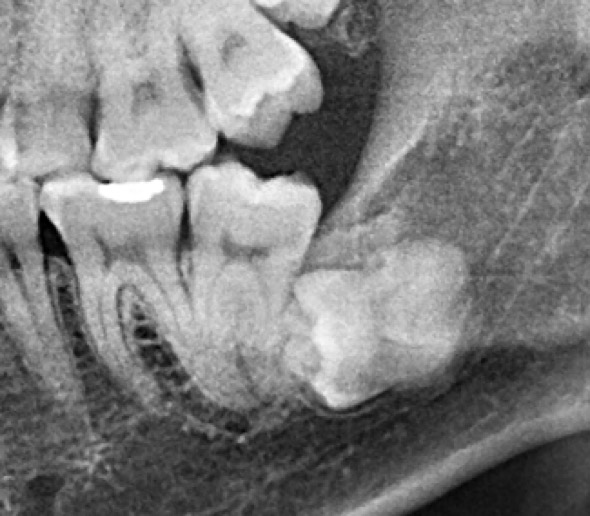

(兩條紅線中間黑色區域即為神經管)

外面拔完時常術後唇麻舌麻,本院發生趨近於零